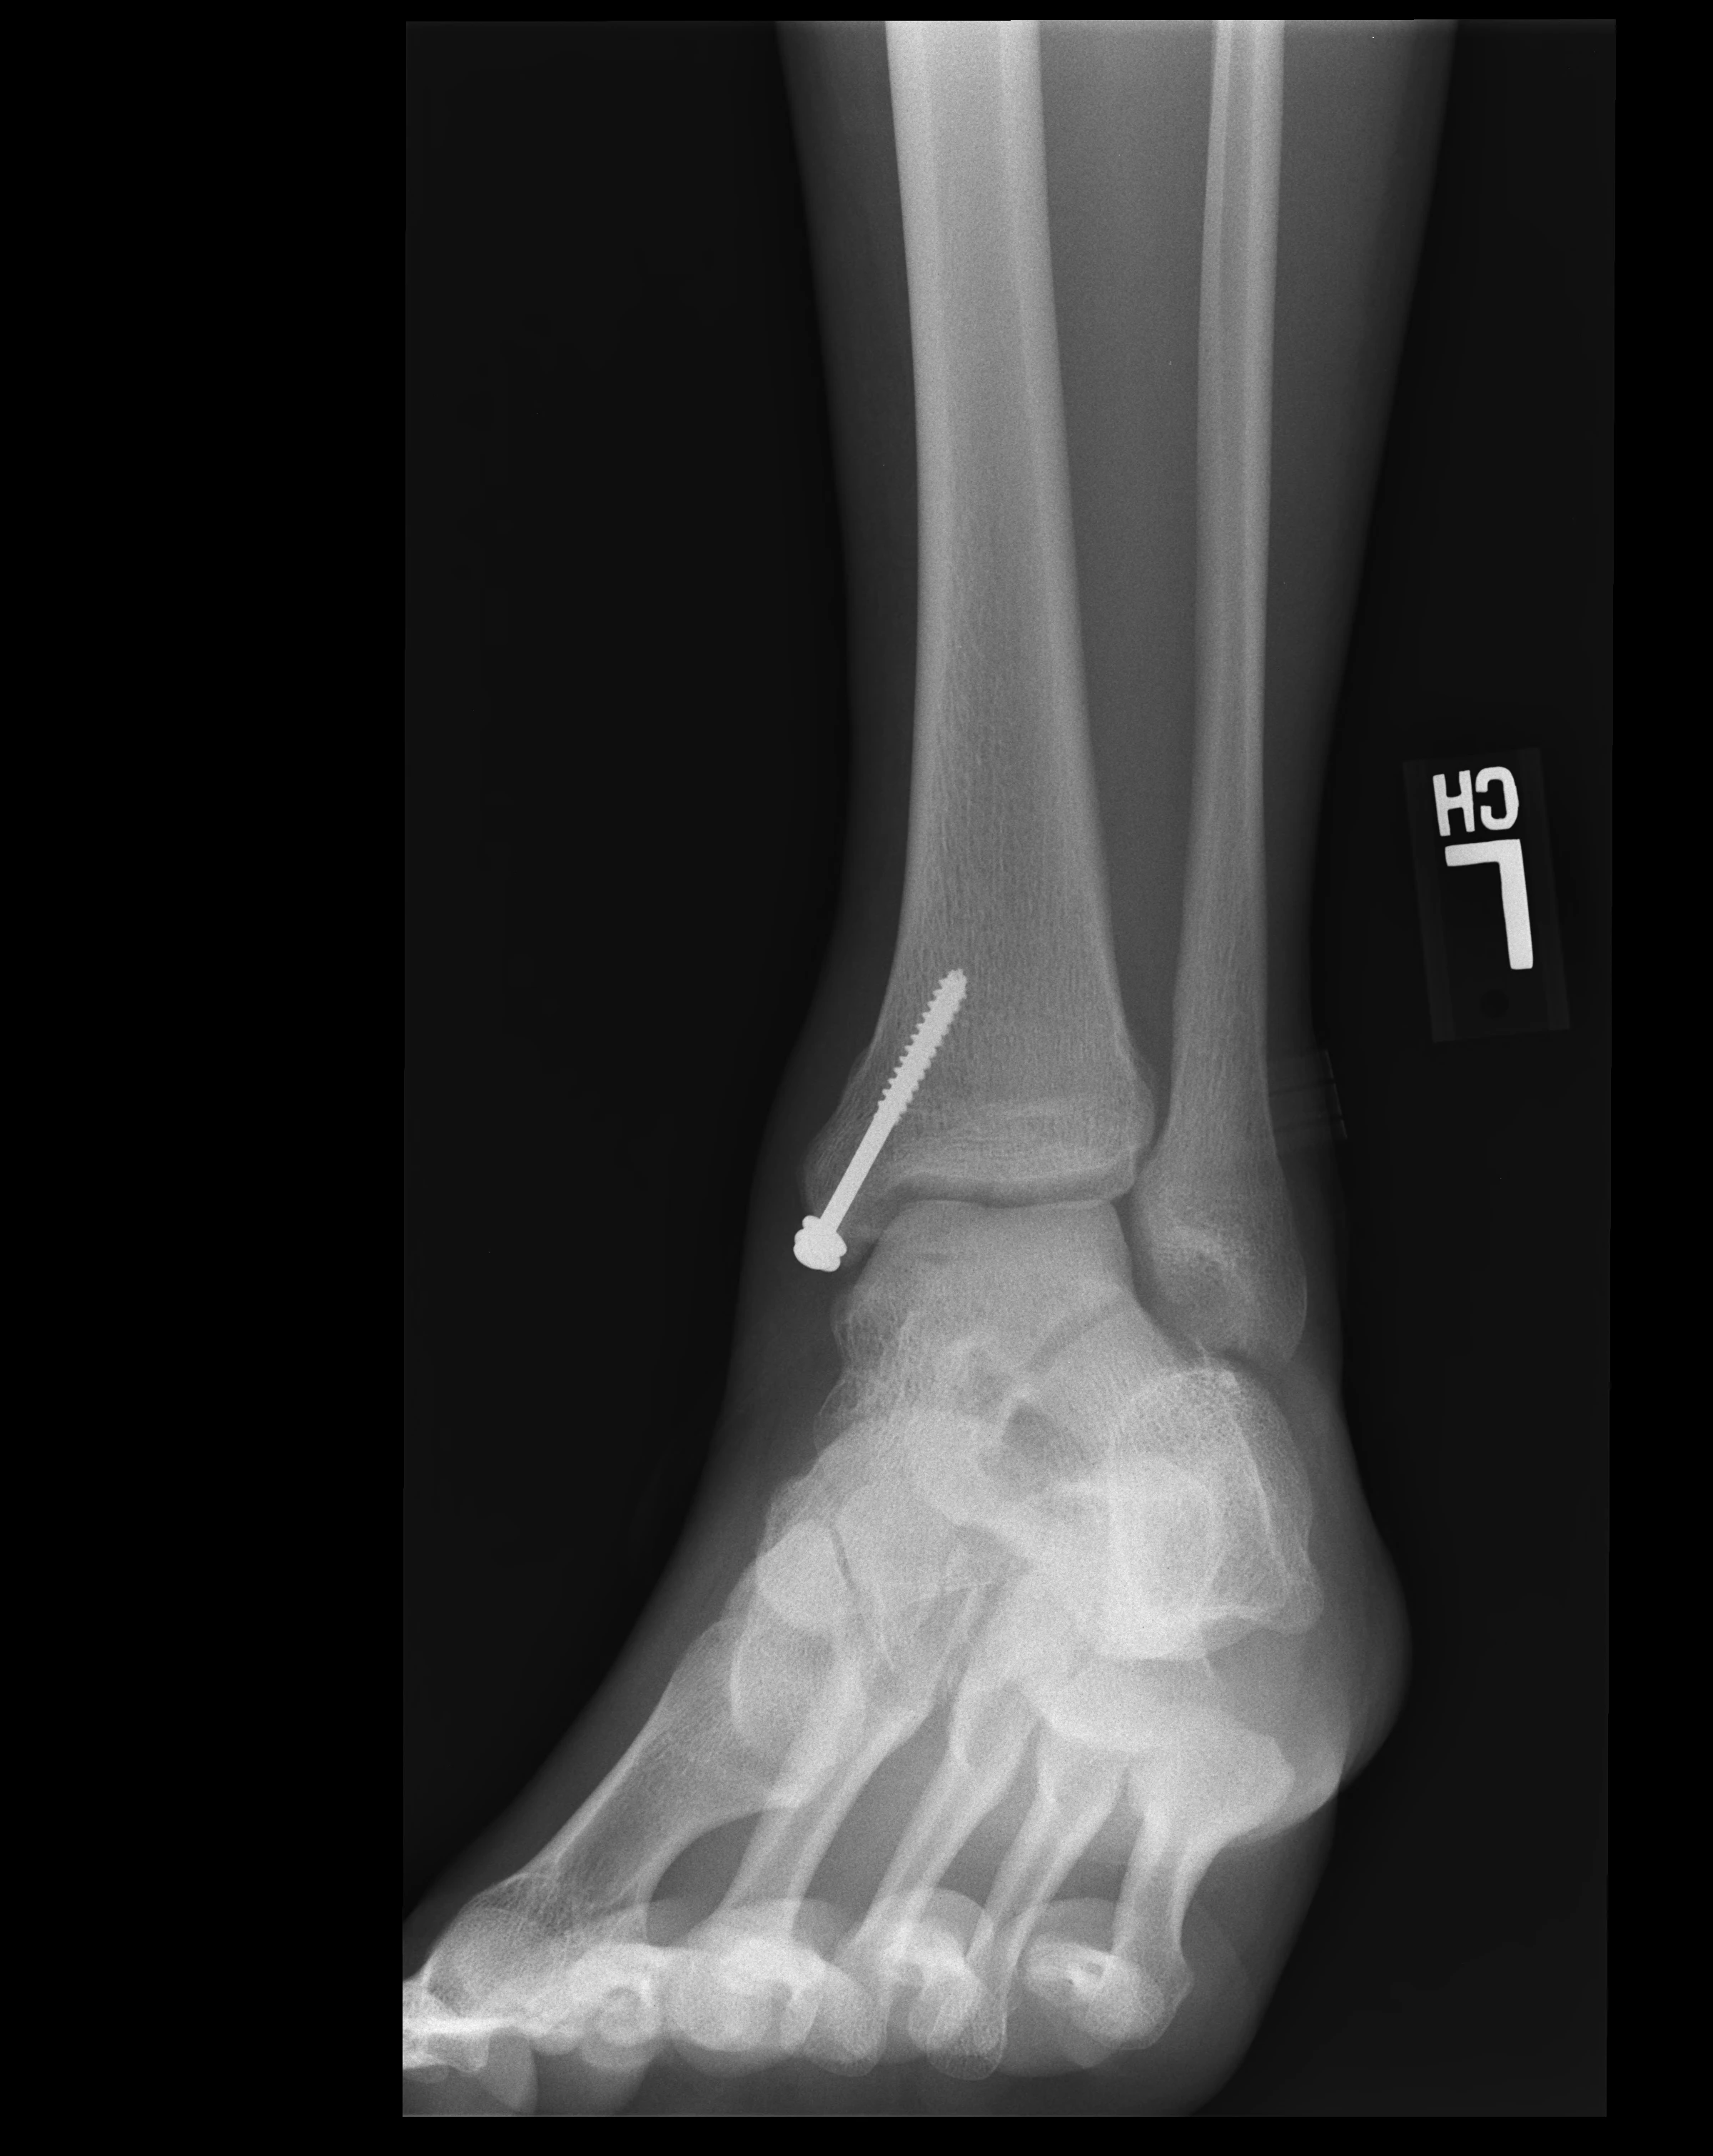

• Ordered standing X-rays: Weight-bearing X-rays to observe the ankle joint under load

• X-ray results: The follow-up x-rays show good preservation of ankle joint space

• Medial malleoli osteotomy healed with anatomic alignment and stable hardware

→ The bone that was cut to access the ankle has healed perfectly; screws are solid

• Post-operative changes of ORIF of medial distal tibia with two screws; no residual fracture plane visualized

→ The two screws from surgery are visible; the bone they fixed has healed completely